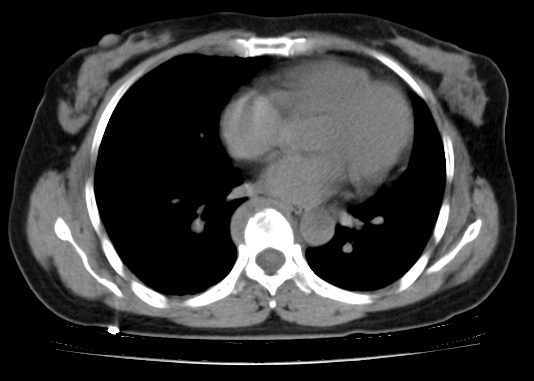

标题: CT25227:背部疼痛伴双侧胸壁痛2月,食欲差。 [打印本页]

标题: CT25227:背部疼痛伴双侧胸壁痛2月,食欲差。

肺结核并胸椎结核?请各位高手指教。

用椎体的条件来扫胸椎呀!考虑1左侧胸膜小结节形成2椎体结核并冷脓肿形成

左肺结核灶,胸椎结核并冷脓肿。

左肺结核灶,胸椎结核并冷脓肿

食道癌并胸椎及肺内转移